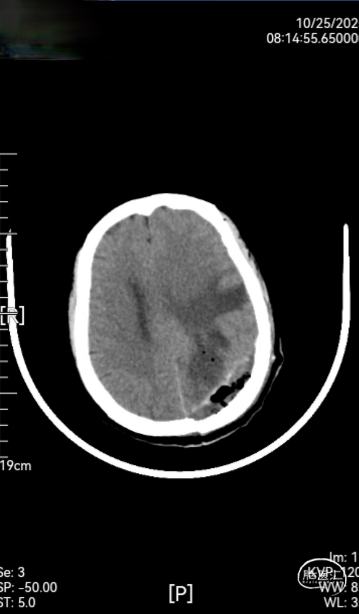

➤ 术后检查:术后第2天,第8天,第12天复查头颅CT(如图3),术后术区无渗血,骨瓣固定良好,无错位及膨出,且CT无伪影,患者顺利出院。

图3:术后第2天,第8天,第12天复查头颅CT